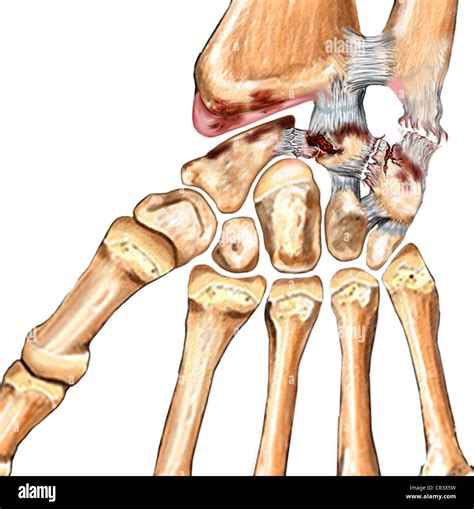

The ulnar collateral ligament consists of three distinct bundles: the anterior, posterior, and transverse bands. The anterior bundle is the most vital for elbow stability, especially when the arm is extended. This ligament acts as a tether, preventing the elbow from shifting outward when force is applied to the outside of the arm—a mechanism known as valgus stress.

When the stress applied to the ligament exceeds its tensile strength, micro-tears can develop over time, eventually leading to a complete rupture. While professional baseball pitchers are the most frequent victims of this injury due to the repetitive, violent nature of throwing, a ruptured ulnar collateral ligament can occur in any individual who experiences a traumatic fall on an outstretched hand or engages in sports involving intense overhead or twisting motions.